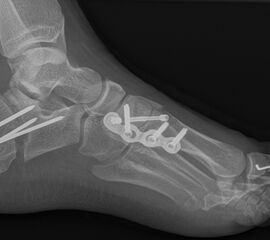

Calcaneus-Osteotomie

Die minimalinvasive Calcaneusverschiebeosteotomie bietet eindeutige Vorteile gegenüber dem offenen Verfahren, sodass wir bei Kindern und Jugendlichen nahezu keine offene Verschiebeosteotomie mehr durchführen. Am Calcaneus liegt die offene Wachstumsfuge dorsal. Bei der Durchführung müssen Schenkel der V-förmigen Osteotomie daher etwas steiler angelegt werden, in einem stumpfen Winkel (siehe Abb. 3 a-j). Für die Osteotomie liegen unsere Patienten auf dem Rücken und der BV wird für die exakte Seitaufnahme eingestellt. Der Fuß lagert auf einem hohen OP-Kissen und die Osteotomie kann bequem mit einem langen Kirschner-Draht und einem sterilen Stift angezeichnet werden (Abb. 15).

Damit lässt sich im Verlauf Röntgenstrahlung für die jungen Patienten vermeiden und die minimalinvasive Osteotomie kann sicher durchgeführt werden. Anschließend erfolgt die Verschiebung oder Impaktion. Ist ein Gleiten nach plantar oder cranial des distalen Fragmentes erwünscht, wird die Osteotomie schräg ohne V-Form entweder verlängernd oder verkürzend durchgeführt (Abb. 16).

Durch den knöchernen Defekt der Fräse gelingt die Verschiebung bei der minimalinvasiven Osteotomie im Fall von strukturell festen Klumpfüßen mit starkem Zug der verkürzten Achillessehne oder bei einer fixierenden spastischen Grunderkrankung einfacher gegenüber dem offen Verfahren. Ein weiteres Plus bei hyperaktiven Weichteilen ist die Vermeidung der ungewollten Cranialisierung des dorsalen Fragmentes durch die V-förmige Osteotomie (Abb. 16).

Die minimalinvasive Calcaneusverschiebeosoteotomie kommt somit in der Versorgung von kindlichen und jugendlichen Fußdeformitäten in einem weiten Erkrankungsspektrum zum Einsatz (Abb. 16):

- Plattfuß – Varisation

- Klumpfuß residual – Valgisation und ggfs. Cranialisation sowie Impaktion

- Klumpfuß überkorrigiert – Varisation und ggfs. Plantarisierung

- Hohlfuß – Cranialisation und ggf. Valgisation (alternativ minimalinvasive Austin-Osteotomie)

Abb. 16 a-f: Varisation einer valgischen Calcaneusstellung bei Knick-Senk-Fuß mit V-förmiger Osteotomie axiale Ansicht (a), seitliche Ansicht (b), d. p. Ansicht (c) und nach Entfernung der Drähte seitliche Ansicht (d), Caudalisierung des dorsalen Calcaneus bei iatrogenem Plattfuß nach Klumpfußüberkorrektur (e) und Cranialisierung beim Hohlfuß (f).

Zum Lesen der Bildbeschreibung und zur Vollansicht bitte die Bilder anklicken. Bilder: A. Helmers.